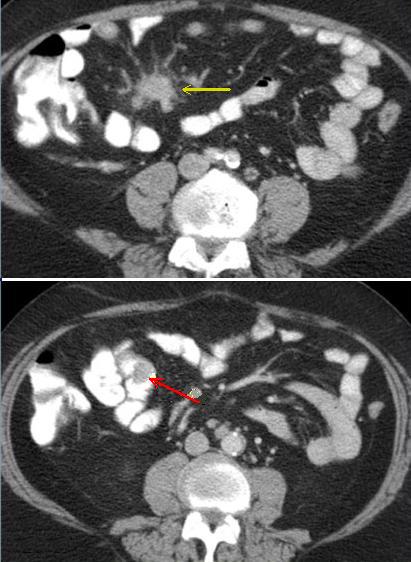

| Tumeur a petite taille

hypo-dense intraluminale de l'intestin ( fleche

rouge ) avec image

d'une masse spicule ( fleche jaune ) mesenterique ( reaction

desmoplastique adjacent ) |

Masse fibrose par

desmoplastique meseterique en forme de

image spiculaire ( fleche rouge ) d'une tumeur

carcinoide de l'intestin . Image TDM en coupe

coronal |

Image TDM axiale : Tumeur multicendrique ( fleche

rouge ) et masse a hyper-dense retractile de

mesentere . Tumeur carcinoide . |